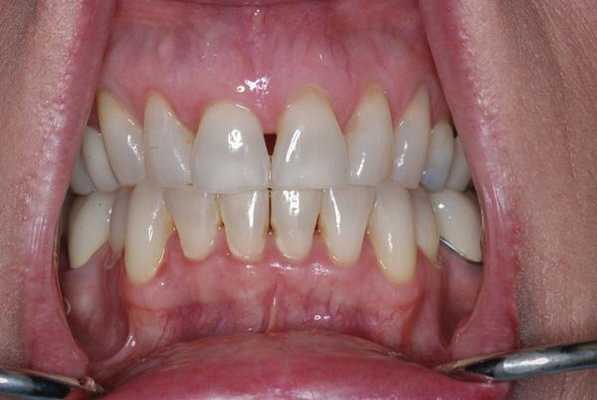

При уменьшенном слюноотделении слизистая оболочка полости рта становиться сухой и в ходе диагностике к ней могут прилипать перчатки, валики и даже стоматологические зеркала. На спине языка могут визуализироваться нитевидные сосочки и трещины, наличие которых позволяет поставить диагноз волосатого языка (фото 1). В пришеечных областях зуба часто визуализируются участки кариозного поражения (фото 2), небольшие эритематозные пятна диагностируются на слизистой щеки, где также могут присутствовать следы накусывания от зубов (фото 3). У пациентов также могут отмечаться признаки гингивита, рецессии и пародонтита (фото 4).

Фото 4. Признаки гингивита при выраженной гипофункции слюнных желез.